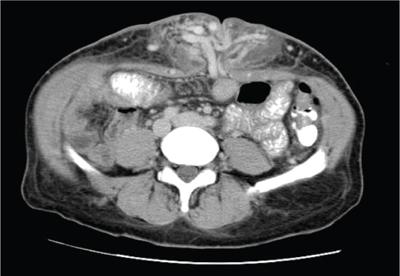

Shrinivas B. Desai, Ritu K. Kashikar, Shreya Shukla Radiological signs are classical and distinctive abnormalities characteristic of a disease. These can be seen on any imaging modality. Resemblance to commonly seen objects and patterns form the basis of radiological signs. The aim is to help the reader associate, understand and memorize these pathologies with the aid of signs. Various signs pertinent to hepatobiliary system are described in the chapter. Described on MRI when liver lesion shows a peripheral rim of high T2 signal intensity with the centre of the lesion appearing isointense to the background of noncirrhotic liver on T2WI mimicking an atoll. It is considered a characteristic sign of an inflammatory hepatic adenoma (image) but is only seen in about one-third of cases Extrinsic smooth impression over medial aspect of duodenum along its posteroinferior aspect, seen in pancreatic head pathologies like carcinoma. This sign is seen in pancreatic adenocarcinoma Presence of a persistently hyperattenuating dot within a lesion on arterial and portal venous CT. This corresponds with peripheral nodular enhancement seen on dynamic MR. Presence of bright dot suggests that the lesion is a hemangioma and helps in ruling out metastasis Ultrasound appearance of multiple cystic spaces or lesions that has been used to describe the appearance of an intraductal papillary mucinous neoplasm of the pancreas. Seen on contrast CT in portal hypertension. The appearance is based on resemblance to Medusa from Greek mythology. Dilated engorged paraumbilical veins radiating across umbilicus to join systemic veins is seen. This sign is seen in Caroli’s disease on contrast CT. Enhancing dots within dilated intrahepatic bile ducts represent portal radicles. Caroli’s disease Irregularly dilated pancreatic duct with multiple strictures and intervening dilatation with associated dilated side ductules resemble multiple lakes supplied by a single territory. Best seen in MRCP images. Chronic pancreatitis It is a finding on MRI and CT and is best seen on MRI T2-weighted and postcontrast T1-weighted sequences. Small necrotic/purulent areas in the pyogenic abscess ‘cluster’ together and then coalesce into a larger necrotic/purulent areas, eventually becoming a larger septated abscess cavity. At the periphery of these clusters: Associated with pyogenic hepatic abscesses and can help differentiate pyogenic abscesses from other types of liver lesions Abrupt termination of gas within the proximal colon at the level of radiological splenic flexure. The inflammatory exudates in pancreatitis extend to the phrenicocolic ligament giving rise to this sign Seen on grey scale ultrasound as a reverberation artifact when small calcific or highly reflective objects are imaged. The colour comet-tail artifact is an ultrasonographic sign seen in a number of situations when colour Doppler scanning is performed. This sign occurs in cases of traumatic right-sided diaphragmatic rupture with resultant partial herniation of liver through the defect. Separation of the herniated liver from its intra-abdominal component is via a small constriction at the level of diaphragm resembling a cottage loaf. Cottage loaf is a particular shape of bread in which larger and smaller roughly spherical balls are squashed together. Traumatic right-sided diaphragmatic rupture with resultant partial herniation of liver Bile eccentrically outlines luminal stone, creating a low attenuation crescent. Best seen on MRCP images. Choledocholithiasis Dilatation of both pancreatic duct and CBD is referred to as the double duct sign. Positive double duct sign suggests the diagnosis of carcinoma of the head of the pancreas and ampullary tumours and is hence considered ominous. Occasionally the sign may be seen in impacted gallstone in the distal duct. This feature is seen in patients with liver abscess on contrast-enhanced CT. A double, inner hyperattenuating and outer hypoattenuating rim is seen surrounding the hypodense abscess. The inner hyperattenuating rim corresponds to the enhancing abscess membrane, while the outer rim corresponds to the edema of the surrounding liver which appears hypodense and may show delayed enhancement. Liver abscess A positive duct penetrating sign is when a mass is penetrated by an unobstructed pancreatic duct; this makes focal pancreatitis the most likely cause rather than pancreatic carcinoma. This sign is best appreciated on MRCP (or ERCP). A radiographic sign that can be useful in differentiating between focal pancreatitis (inflammatory pancreatic mass) from pancreatic carcinoma. The duct-penetrating sign on MRCP is more helpful in differentiating between these two entities than a delayed enhancement pattern on CT or MRI It occurs when there is both limy bile and a gallstone in the common bile duct. The linear vertical radiopaque bile forms the line of the exclamation mark (i.e. !), whilst a more distal calculus forms the ‘dot’ at the end of the exclamation mark. Pathognomonic imaging sign of the rare diagnosis of limy bile on plain abdominal radiography Nonenhancing ruptured lesion with peripheral rim enhancement showing discontinuity from the rest of the liver and protruding from the liver surface is called the enucleation sign. Ruptured HCC Enlargement of the pericholecystic space. One of the signs of liver cirrhosis Can be seen on technetium 99m sulphur colloid scans of the liver and spleen, as well as CT studies. It occurs as a focal area of increased radiopharmaceutical uptake in the medial segment of the left hepatic lobe (segment IV) occurring as a result of SVC obstruction and portosystemic venous shunting between the superior vena cava and the left portal vein via the internal thoracic and paraumbilical veins. The equivalent of this sign may also be seen on contrast-enhanced CT scans as a hypervascular region. Budd–Chiari syndrome causes the hot spot sign in the caudate lobe

5) Caput medusae sign